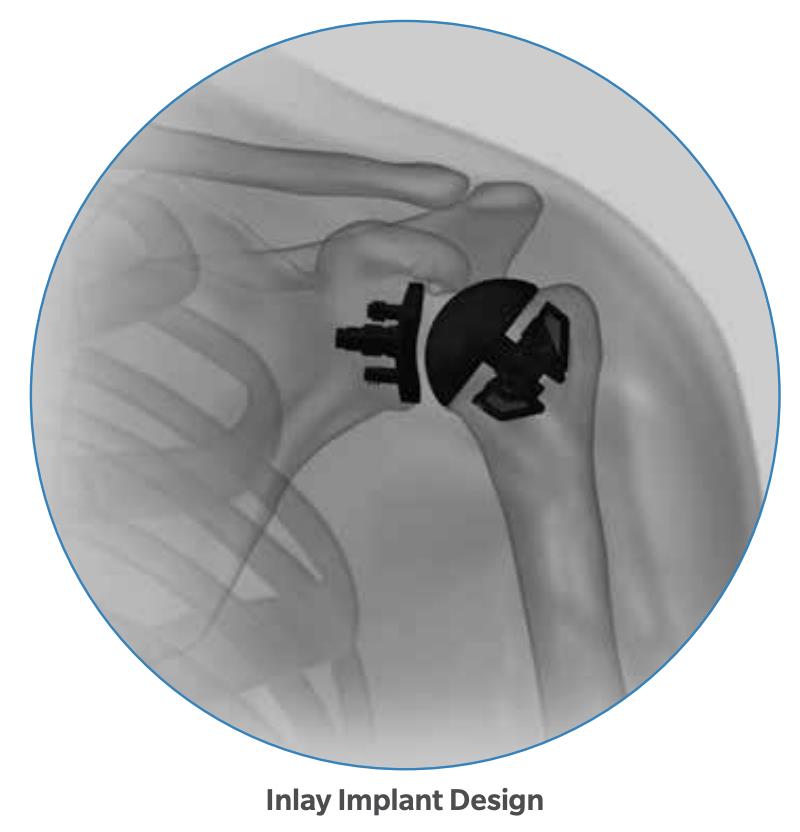

Summary The OsseoFit™ Stemless Shoulder System is indicated for anatomic total shoulder arthroplasty in patients where a bone-sparing, stemless solution is desired to maximize humeral fixation. It achieves this through OsseoTi® Porous Metal Technology and a site-specific fin design that creates a stable, biological press-fit while simplifying the surgical workflow with integrated suture holes. This system addresses a wide variety of patient anatomies using its versatile inlay and onlay size options. Indications Indications osteoarthritis indicated for anatomic total shoulder applications Contraindications local/systemic infection, sepsis, and osteomyelitis active local or systemic infection sepsis osteomyelitis inadequate humeral bone inadequate bone may lead to poor implant fixation large metaphyseal cysts may compromise stemless fixation irreparable cuff tear rotator cuff must be functionally reconstructable for anatomic total shoulder arthroplasty revision of any stemmed or stemless prothesis contraindicated for revision of any stemmed or stemless prosthesis Anatomy Osteology humeral head anatomic neck greater tuberosity lesser tuberosity bicipital groove metaphyseal cancellous bone Muscles deltoid forms the lateral border of the deltopectoral interval pectoralis major forms the medial border of the deltopectoral interval subscapularis released and repaired according to surgeon preference Ligaments glenohumeral capsule is released as needed to expose the humeral head and glenoid coracohumeral ligament contributes to rotator interval constraint superior, middle, and inferior glenohumeral ligaments contribute to anterior stability transverse humeral ligament overlies the bicipital groove Nerves axillary nerve courses inferior to the subscapularis and around the lateral humerus must be protected musculocutaneous nerve lies medial to the coracobrachialis and conjoint tendon suprascapular nerve is at risk with aggressive posterior-superior glenoid exposure Blood supply anterior and posterior humeral circumflex arteries arcuate artery is a terminal branch of the anterior humeral circumflex system suprascapular and circumflex scapular vessels Preoperative Planning X-rays A/P, scapular Y and axillary views evaluate bony anatomy, humeral head position, glenoid wear, deformity, and acquired bone loss use x-ray templates to estimate stemless humeral implant size assess whether an anatomic total shoulder reconstruction is appropriate CT assess bone quality and identify any humeral bone tissues use to assess bone quality and identify humeral bone issues that may affect implant selection evaluate metaphyseal bone stock, cysts, avascular necrosis, deformity, and cortical support Approach Extended deltopectoral anterior incision with an optional biceps tenodesis beginning immediately above the coracoid process and extending distally and laterally, following deltopectoral groove along the anterior border of the deltoid Technique Humeral head resection expose the humeral head and identify anatomic neck landmarks fixed-angle resection targets 135° inclination and 30° retroversion select left- or right-specific extramedullary resection guide align the guide post with the humeral shaft for fixed-angle resection align the 30° version rod with the forearm flexed at 90° place pins to define version and inclination and to stabilize the cutting surface resect the humeral head through the far side of the humeral head adjust the resection with the guide or calcar planer if needed assess bone quality with direct pressure perpendicular to the resected surface consider stemmed humeral fixation if cancellous bone is easily depressed or primary stability is questionable Humeral protection during glenoid preparation select the humeral resection cover that most closely fits the resected surface prepare the glenoid using the appropriate compatible glenoid technique remove the humeral resection cover before humeral sizing Humeral sizing place the humeral sizer onto the resection surface select the size intended to optimize cancellous bone fixation without violating the inner cortical rim orient the sizer so the bicipital groove bisects the superior and anterior fins insert the central Steinmann pin through the center of the sizer and through the lateral cortex avoid deep lateral cortical penetration to reduce risk to the axillary nerve place a lateral humeral retractor as needed to protect the axillary nerve confirm sizing after any additional planing Humeral bone preparation (boss reaming) ream until the boss reamer bottoms out on the resected surface ream over the central Steinmann pin with the boss reamer protect the lateral humerus and axillary nerve with a retractor remove the boss reamer while leaving the central Steinmann pin in place Humeral bone preparation (broaching) select the reference foot based on implant size select the broach that corresponds to the humeral sizer align the broach superior fin with the superior indicator line on the broach inserter slide the assembly over the central Steinmann pin until the broach contacts the resection surface remove the inserter-reference foot assembly and central Steinmann pin perform broach stability testing consider stemmed humeral fixation if the broach is unstable Humeral head trialing determine humeral head diameter and height using the humeral head sizing template or the resected humeral head seat the head trial assembly into the broach rotate the trial assembly with the hex driver to assess coverage of the resection surface confirm alignment with the anterior and posterior borders of the humeral resection increase offset if the head trial does not cover one side of the resection decrease offset if the head trial overhangs the resected bone reduce the joint and perform trial range of motion record the final offset letter or interval on the proximal humerus remove and disassemble the head trial assembly Implant insertion remove the broach with the slap hammer while maintaining an on-axis trajectory use the same reference foot size used for broach insertion select the implant size corresponding to the final broach and operative side slide the reference foot down until it uniformly contacts the resection surface confirm superior fin markings on reference foot, implant, and bone are aligned disengage the inserter-reference foot assembly with axial traction and slight rotational force as needed onlay implant center boss is slightly proud of the resection surface, with fin top surfaces flush inlay implant sits below the resection surface Humeral head implantation select the final humeral head implant matching the trial diameter and height use the offset letter or interval determined during trialing place the humeral head into the concave surface of the impactor base on a rigid sterile table impact the adapter into the humeral head with the disposable impactor using a mallet, strike the head impactor at least twice until the humeral head is flush with the resection visually confirm uniform seating consider implant subsidence and stemmed fixation if no pre-impaction gap is present Technical specifications Implant design anatomically shaped asymmetric anchor design designed to match natural asymmetric humeral anatomy designed to maximize cancellous bone fit and help avoid cortical impingement six-fin configuration with progressive tapered wedge design fins are designed for press-fit insertion each fin contains a fully porous window anterior suture holes are present for subscapularis repair Porous technology OsseoTi® Porous Metal Technology is used in the stemless implant porous architecture is designed to mimic human cancellous bone design incorporates a fully porous 3D printed OsseoTi® lattice within a titanium framework Technical specifications OsseoFit Onlay Anchor Implant Side Size Left 1, 2, 3, 4, 5 Right 1, 2, 3, 4, 5 OsseoFit Inlay Anchor Implant Side Size Left 1, 2, 3, 4, 5 Right 1, 2, 3, 4, 5 OsseoFit Humeral Head Adapter